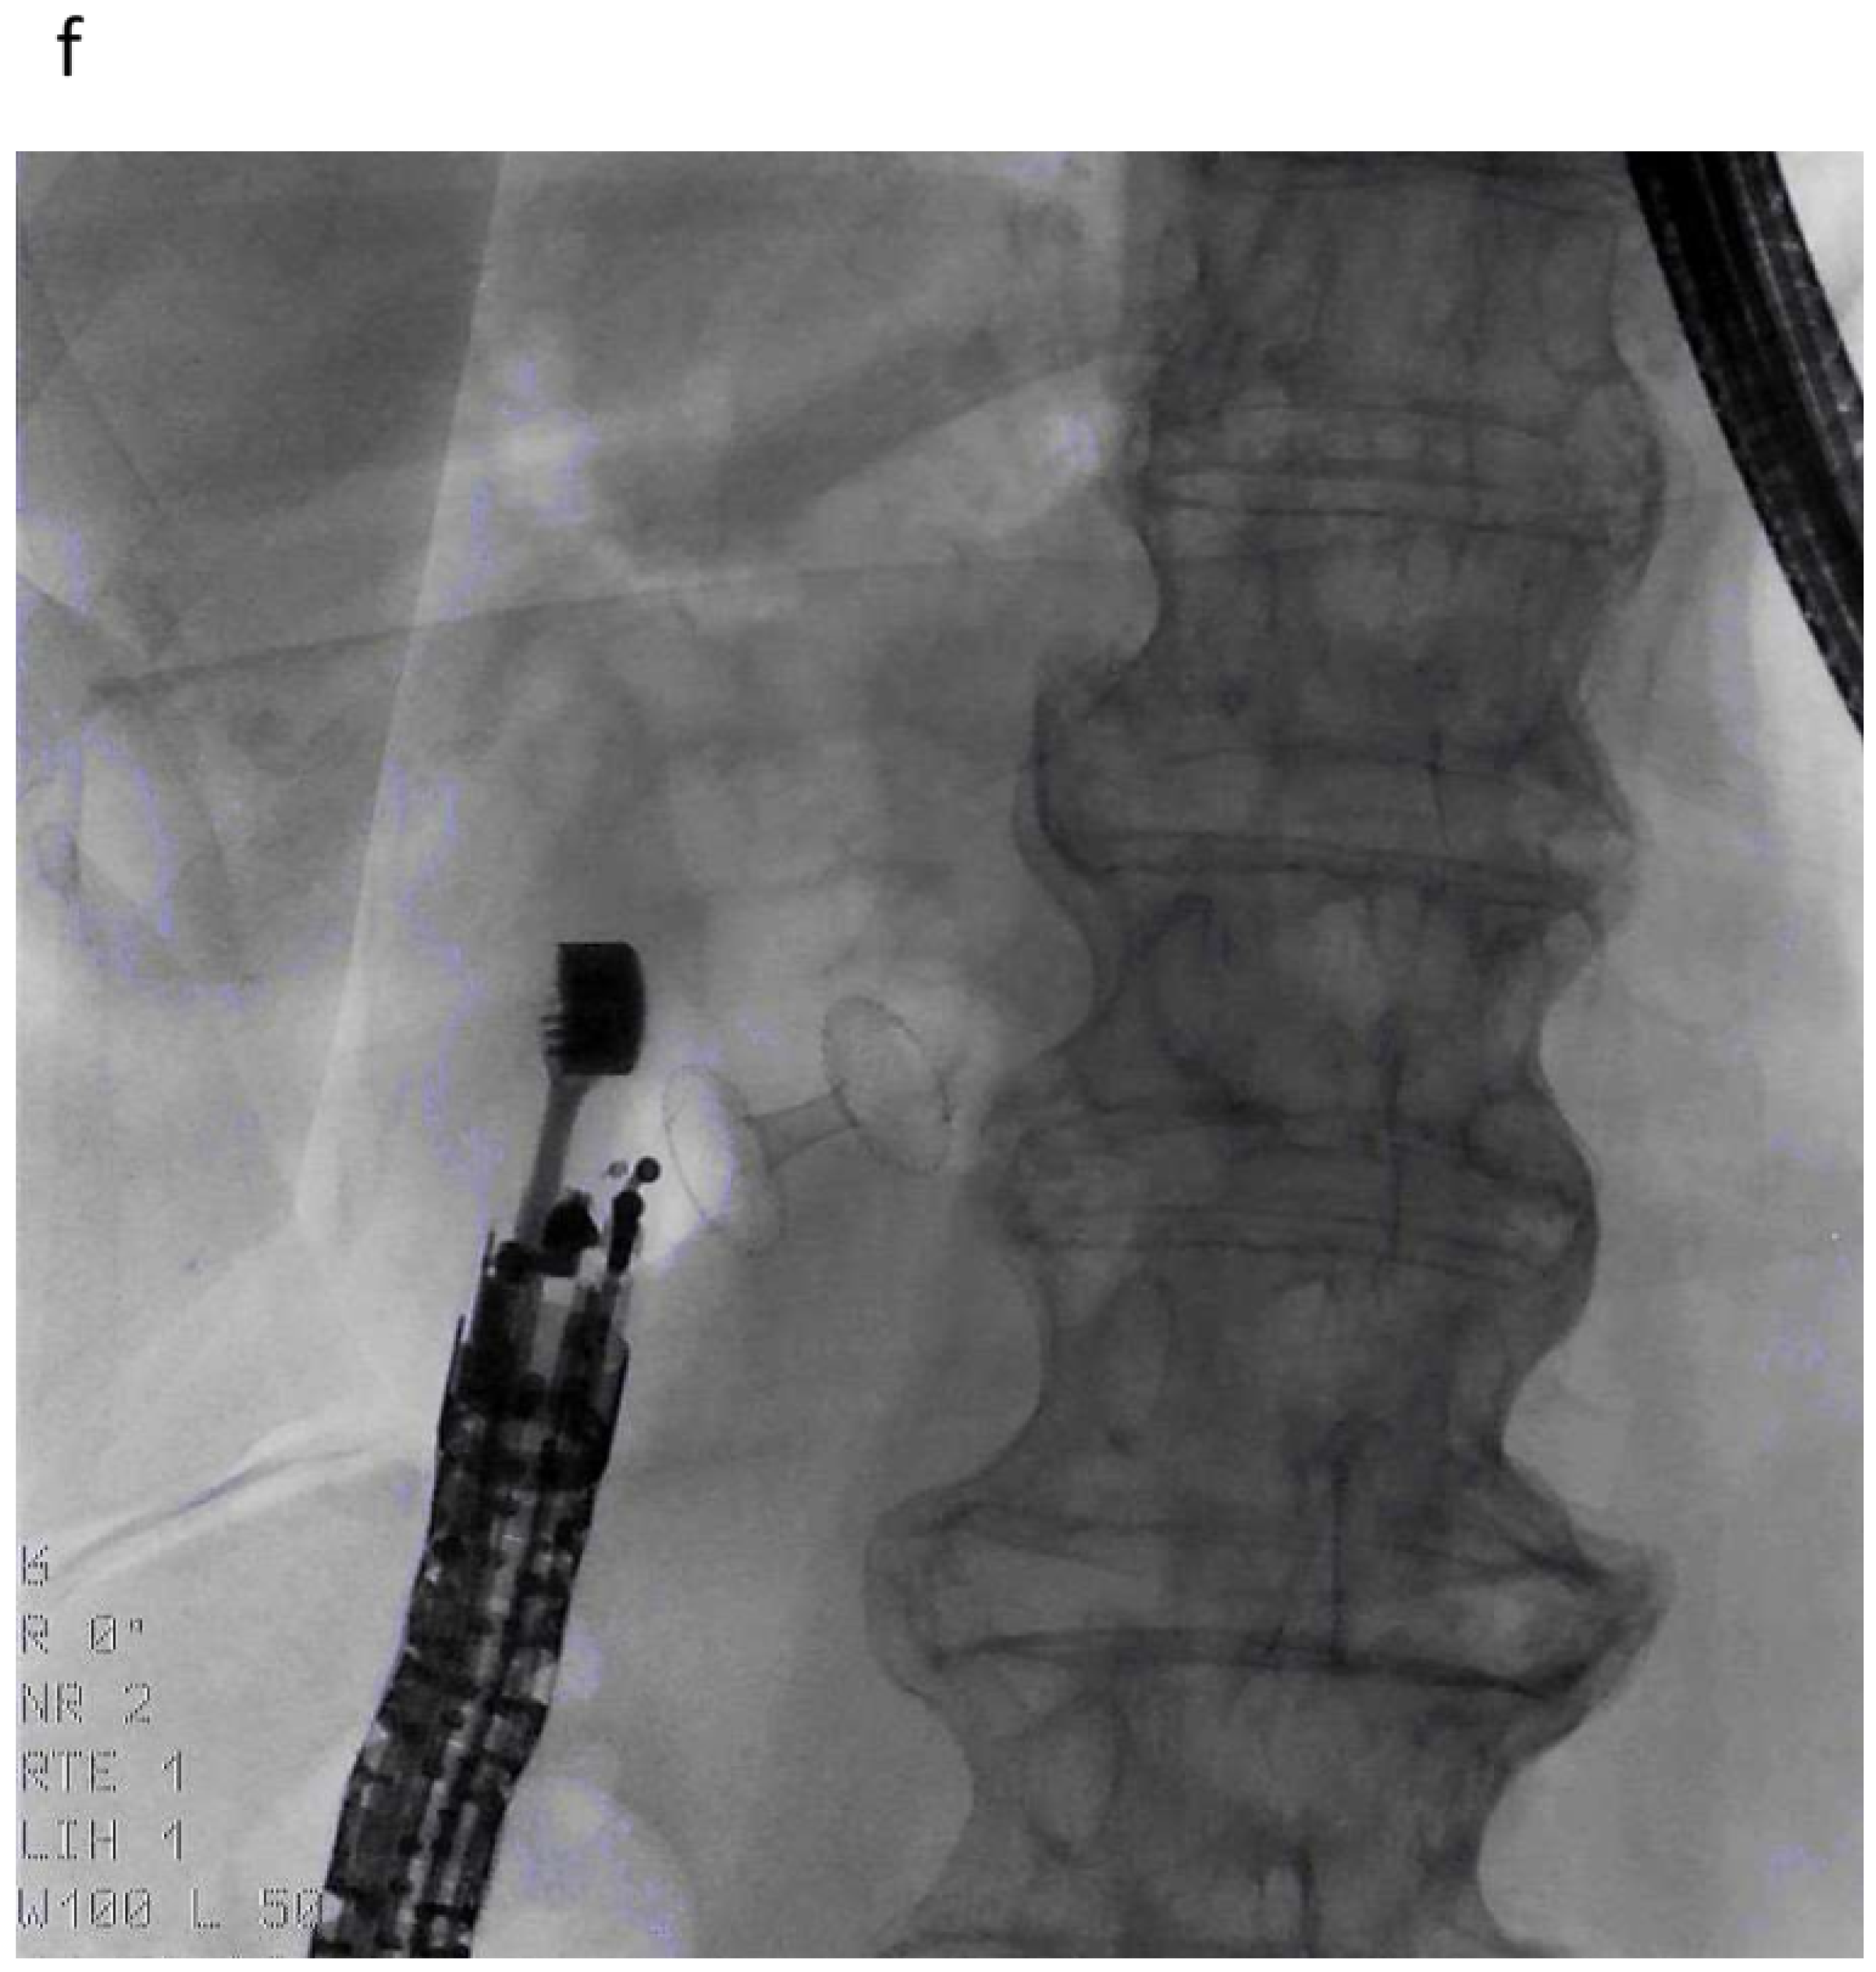

3.1.1. EUS-BD of the Bile Duct

3.1.2. EUS-GBD

3.2. Arguments against EUS-Guided Drainage